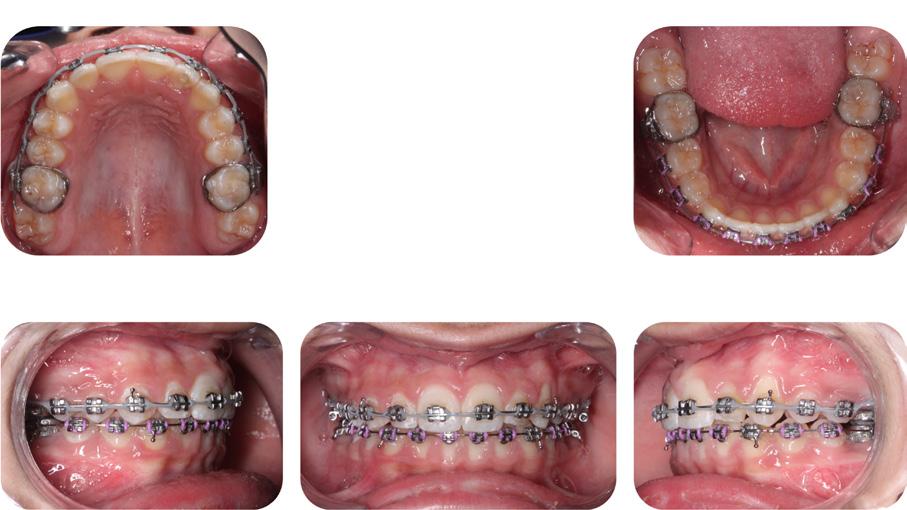

Please view the post-treatment images at the time of insertion of the retainers (Figure 14 - A, B, C. D, E, F, G, H, I, J, K, L, M, N).9

Figure 14H: Post-treatment, mandible, occlusal view

Figure 14G: Post-treatment, occlusal view